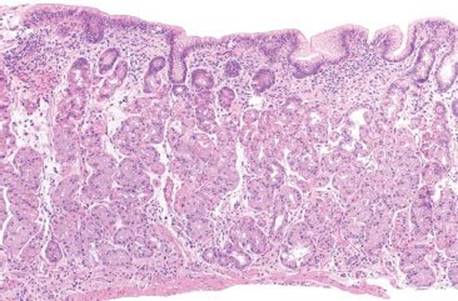

Figure 2.132 Lymphocytic gastritis pattern, celiac disease. This patient has an established history of celiac disease with poor adherence to a gluten-free diet. The IELs seen in the gastric mucosa are believed to result from the same immunologic process as seen in the duodenum. Some studies have correlated more severe small bowel disease in patients who demonstrate lymphocytic gastritis.